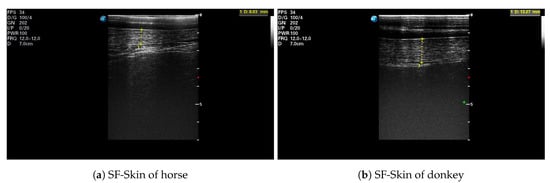

After each IRT imaging, an ultrasonographic image was taken with an ultrasound scanner (SonoScape S9, SonoScape, Shenzhen, China) using a linear 5–12 MHz transducer (L752, SonoScape, Shenzhen, China). Ultrasound scans were performed with the transducer placed on the animal’s back, over the third lumbar vertebra, perpendicular to the spine. All images were collected on the left side of the animal [37]. The hair was trimmed at the measurement place, and ultrasound gel (Aquasonic 100, Parker Laboratories Inc., Fairfield, NJ, USA) was used as a coupling medium. The real-time ultrasonographic examination was frozen, and the image was saved, as well as the subcutaneous fat (SF) plus skin thickness (SF-Skin) measurements were obtained. An example of an ultrasonographic image is presented in Figure 1. The hair coat samples were taken from the mid-neck approximately 5 cm below the base of the mane. The length of individual hairs was determined from a random sample of five pulled strands, including the roots [38].

Figure 1. Example of an ultrasonographic image taken over the third lumbar vertebra: (a) the horse H.1; (b) the donkey D.3. The subcutaneous fat plus skin thickness (SF-Skin) is highlighted.